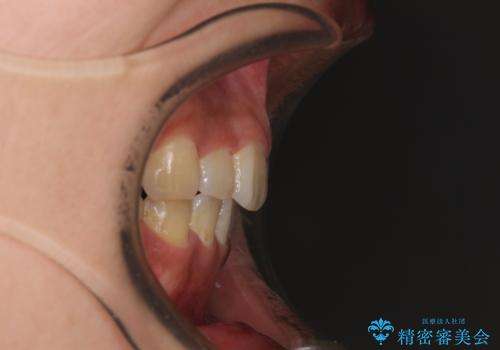

デコボコと膨らんだ口元 ハーフリンガルによる抜歯矯正とインプラント補綴治療

- 前歯のデコボコと上顎の前突感による口の閉じにくさを気にして来院された患者様です。

目立たない装置を希望されたので、上顎が裏側装置のハーフリンガルを選択し、上下左右の小臼歯(計4歯)を抜歯して矯正治療を行うこととしました。

デコボコの解消までは非常にスムーズでしたが、咬合力が強いためか、スペースを閉じるまでに長い期間を要しました。